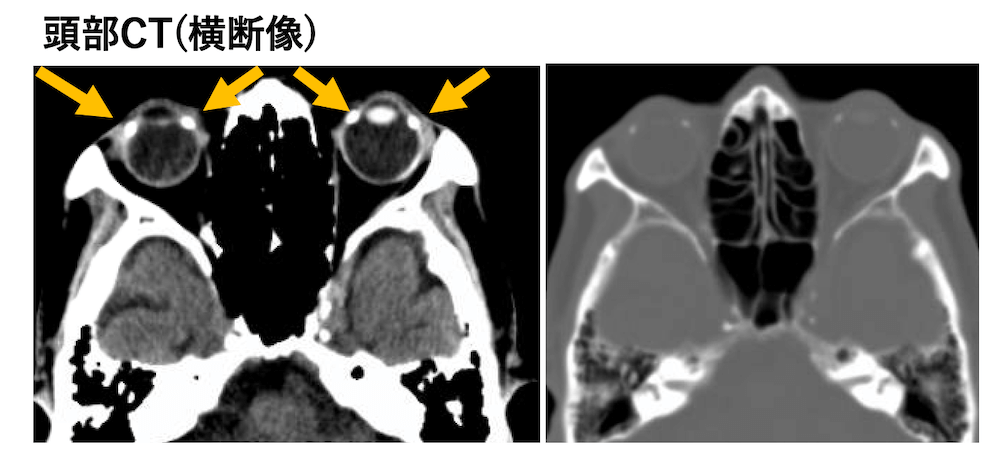

外眼筋の強膜付着部の石灰化

外眼筋の中でも、内直筋・外直筋の強膜への付着部で石灰化が起こり、高齢者に多く、強膜プラークとも呼ばれることがあります。(※アスベストの胸膜プラークとは全く別物です(^_^;))

症例 80歳代男性

右の内直筋・外直筋、左の内直筋の強膜付着部に石灰化を認めています。